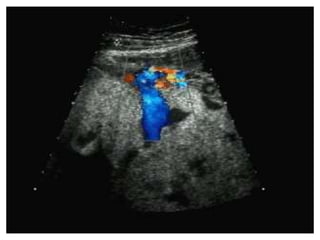

SIGNOS ECOGRAFICOS

• La ecografia posibilita un diagnostico de certeza

casi en la totalidad de los casos.

• La cavidad uterina se encuentra llena de multiples

ecos que dan una imagen caracteristica

tradicionalmente denominada

• Signos ecograficos..

Tormenta de nieve o panal de abejas.

MOLA HIDATIFORME